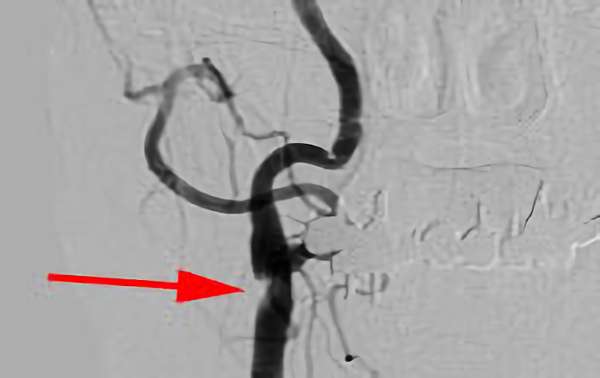

303

'18年11月14日

右内頚動脈狭窄症

70代

大阪府の病院